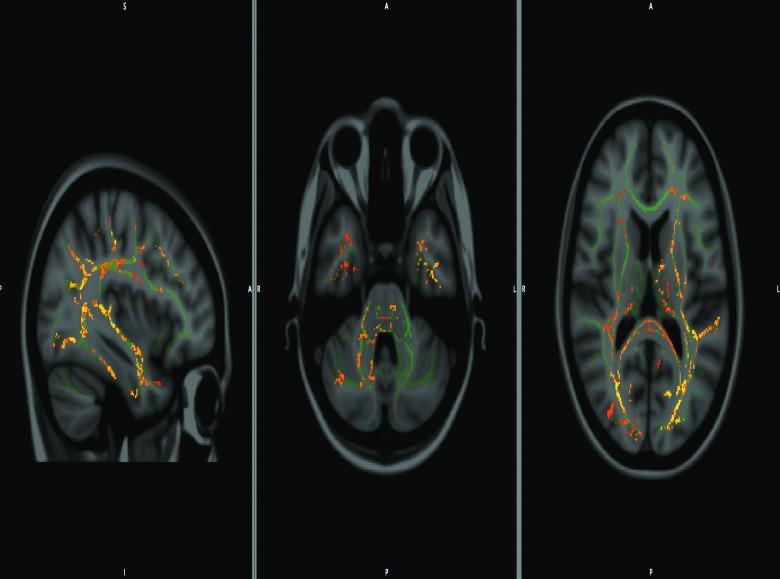

We explored the prognostic value of diffusion tensor imaging (DTI) parameters of selected white matter (WM) tracts in predicting neuropsychological outcome, both at baseline and 6 months later, among well-characterized patients diagnosed with mild traumatic brain injury (mTBI). Sixty-one patients with mTBI (mean age=27.08; standard deviation [SD], 8.55) underwent scanning at an average of 10 h (SD, 4.26) post-trauma along with assessment of their neuropsychological performance at an average of 4.35 h (SD, 7.08) upon full Glasgow Coma Scale recovery. Results were then compared to 19 healthy control participants (mean age=29.05; SD, 5.84), both in the acute stage and 6 months post-trauma. DTI and neuropsychological measures between acute and chronic phases were compared, and significant differences emerged. Specifically, chronic-phase fractional anisotropy and radial diffusivity values showed significant group differences in the corona radiata, anterior limb of internal capsule, cingulum, superior longitudinal fasciculus, optic radiation, and genu of corpus callosum. Findings also demonstrated associations between DTI indices and neuropsychological outcome across two time points. Our results provide new evidence for the use of DTI as an imaging biomarker and indicator of WM damage occurring in the context of mTBI, and they underscore the dynamic nature of brain injury and possible biological basis of chronic neurocognitive alterations.

我们探讨了在确诊为轻度创伤性脑损伤(mTBI)的特征明确的患者中,选定白质(WM)束的扩散张量成像(DTI)参数在预测神经心理学结果方面的预后价值,包括在基线时和6个月后。61例mTBI患者(平均年龄=27.08岁;标准差[SD],8.55)在创伤后平均10小时(SD,4.26)接受扫描,并在格拉斯哥昏迷量表完全恢复后平均4.35小时(SD,7.08)评估其神经心理学表现。然后将结果与19名健康对照参与者(平均年龄=29.05岁;SD,5.84)在急性期和创伤后6个月时进行比较。比较了急性期和慢性期之间的DTI和神经心理学测量结果,出现了显著差异。具体而言,慢性期的分数各向异性和径向扩散率值在放射冠、内囊前肢、扣带、上纵束、视辐射和胼胝体膝部显示出显著的组间差异。研究结果还表明,在两个时间点上,DTI指数与神经心理学结果之间存在关联。我们的结果为DTI作为mTBI背景下发生的WM损伤的成像生物标志物和指标提供了新证据,并强调了脑损伤的动态性质以及慢性神经认知改变的可能生物学基础。